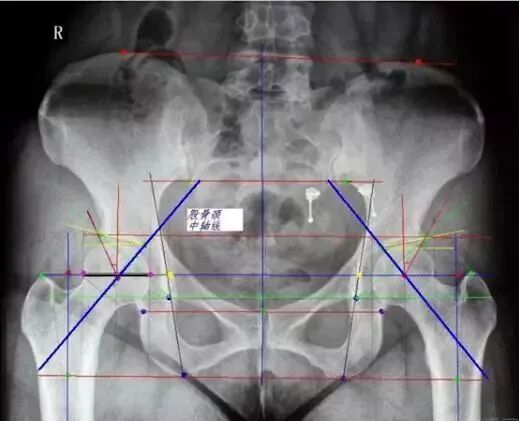

如何从一张普通骨盆片中获取足够信息

中心边缘角(CE角):

髋臼外上缘到股骨头中心连线与垂线所成之角,正常20°~30°,DDH患者此角变小,反应股骨头旋转中心移位程度,小于20°提示先天性髋臼发育不良。

Sharp角:

在骨盆正位片上,双侧泪滴下缘连线与泪滴下缘至髋臼上缘连线的夹角,正常值为33°~38°,此角大于40°提示髋臼发育不良。

髋臼指数:

成年人则为髋臼外上缘到髋臼窝中心连线与水平线夹角。髋关节结构和发育状况的一个重要判断指标。正常髋臼指数为20°~25°,大于25为髋臼发育不良。

髋日深度:

骨盆正位片,耻骨联合上缘与髋臼外上缘连线至髋臼底的最大距离即为髋臼深度。正常成人:男13(7-18)mm,女12(9-18)mm,临床上常与CE角配合使

用表示骨髋臼发育程度。

髋臼覆盖率:

股骨头受髋臼覆盖部分的横径(A)除以股骨头的横径(B),即为髋臼覆盖率,其正常值应大于075。判断股骨头移位情况。

髂坐线 Kohler line:

从坐骨切迹外侧到闭孔内侧。实际反映髋臼底部(中央部、内壁)的缺损深度及范围。髋臼窝超过髂坐线内侧称为突出。

泪滴组成:外侧有髋臼最下部和前部组成,内侧有髂骨四边形骨面的前部组成。呈U形或泪滴形者表明髋臼窝底部骨质较厚,线条形者骨质菲薄,反应底部壁厚度骨量存留。